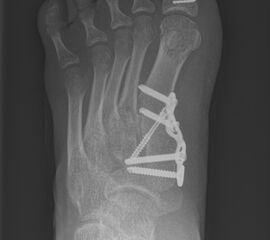

DMMO/DMDO (Distale Minimalinvasive Metatarsale Osteotomie/Distale Minimalinvasive Diaphysäre Osteotomie)

Die Indikation für eine DMMO oder DMDO (Distale Minimalinvasive Metatarsale Osteotomie/Distale Minimalinvasive Diaphysäre Osteotomie) beim Kind mit wachsendem Skelett ist nicht die klassische Metatarsalgie des Erwachsenen. In der Kinderorthopädie kann eine gute Indikation für die DMMO oder für eine DMDO der Ballen-Hohl-Fuß mit Metatarsalgie sein. Wird z. B. bei einer frühen Hohlfußkorrektur das Metatarsale I für eine bessere Rückfußeinstellung extendiert und zur Aufhebung der Extensorensubstitution die Sehne des M. tibialis posterior transferiert, kann sich im Verlauf eine Dysbalance der Metatarsalia entwickeln und eine Metatarsalgie unter II-IV auftreten. Mit einer DMDO werden die Köpfchen II-IV effektiv angehoben und die Beschwerden gebessert (Abb. 17 und 18).

Abb. 17 a-d: Hereditäre Senso-Motorische Neuropathie (HSMN) Hohlfußkorrektur in der frühen Versorgung mittels Metatarsale I Extensionsosteotomie und einem M. tibialis posterior Transfer hälftig auf das Os cuneiforme III und die andere Hälfte eingenäht in den M. tibialis anterior (Steigbügelfunktion) (a-b); intraoperative Bilder nach DMMO rechts kombiniert mit einer Akin-Osteotomie Metatarsale II-III + DMDO MT V und links II-I + DMDO MT V (c-d).

Zum Lesen der Bildbeschreibung und zur Vollansicht bitte die Bilder anklicken. Bilder: A. Helmers.

Abb. 18 a-b: Beispiel einer DMDO beim Hohlfuß d.p. (dorso-plantare) Ansicht (a) und schräge Ansicht (b).